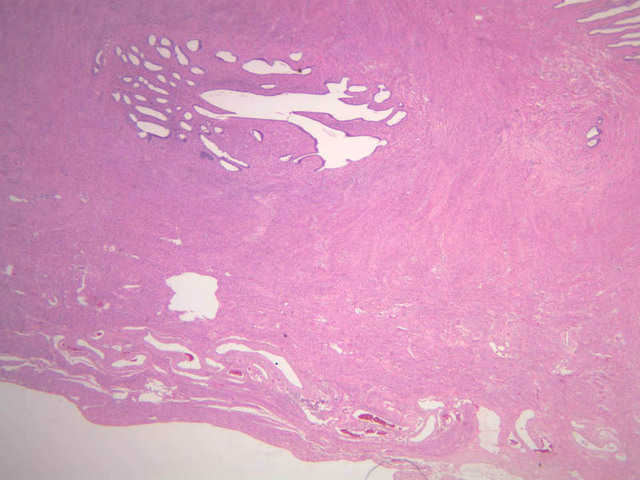

The uterus is a pear-shaped muscular organ, somewhat flattened from front to back. The expanded upper portion is referred to as the fundus, while its lower part, which protrudes into the vagina, is called the cervix. The lumen of the uterus is slit-like and is in communication with that of the uterine tubes (B-97, monkey uterus [1x, 1x, 1x, 1x]). The wall of the uterus consists of three layers: perimetrium, myometrium, and endometrium (B-97 [1x, 1x-labeled] [1x, 1x, 1x]; B-100 [1x, 1x]). The perimetrium is peritoneum which covers the uterus, but is lacking in the posterocaudal third below the peritoneal reflection (B-97 [2.5x, 10x, 20x, 40x]). The myometrium is the very thick middle layer consisting of bundles of smooth muscle cells arranged into several interwoven layers (slide B-93 [1x-labeled, 2.5x] [1x, 2.5x] [1x, 2.5x] [2.5x, 10x, 20x, 40x]). The endometrium is the innermost layer and is a glandular mucosa (B-97 [2.5x, 10x, 20x] [2.5x, 10x, 20x] [2.5x, 10x, 20x, 40x]). It consists of a surface epithelium which is invaginated into tubes called uterine glands. The glands penetrate into a very thick lamina propria referred to as the endometrial stroma. The surface epithelium is a mixture of ciliated and non-ciliated simple columnar cells, whereas the glandular epithelium consists mainly of non-ciliated secretory cells. The endometrial stroma has the appearance of a loose, rather cellular mesenchyme with numerous blood vessels.

The endometrium is subdivided into two main parts; the basalis and the functionalis (slide B-97). The basalis is deep, lying adjacent to the myometrium, it consists of stroma and the closed ends of the uterine glands and is not sloughed during menstruation. The functionalis is upper zone consisting of the remainder of the uterine glands with intervening stroma. It is lost during menstruation, but is replaced again with each menstrual cycle, by proliferation of the persisting elements in the basalis.

The menstrual cycle is a continuous series of events, dominated by the endocrine activity of the ovary, which repeats itself with a 28 day period. The endometrium participates by undergoing a series of structural changes which are roughly divided into three categories, the proliferative, secretory, and menstrual phases. These phases are listed below, examine each of the uterine slides and determine to which phase it belongs.